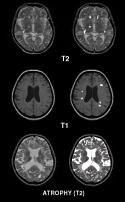

Figure 2. On the left

side, several MRI slices have been segmented in order to

carry out volumetry of Multiple Sclerosis plaques and fluid

spaces. On middle, one segmented slice of a thorax model

is presented together with simulation results. On the rigth

side, various 3D visualization modes of segmented images.

Also multispectral images and more than one modality at

a time can be utilized. For example, MRI scan of the head

can be automatically segmented from T1 and T2 weighted images,

because bone appears black on both image modalities. In